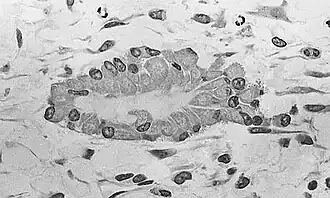

At this stage of development, changes in the morphology of the osteoprogenitor cells occur: Their shape becomes more columnar and the amount of Golgi apparatus and rough endoplasmic reticulum increases. Eventually, all of the cells within the nidus develop into, and display the morphologic characteristics of, an osteoblast. Then the osteoblasts create an extracellular matrix containing Type-I collagen fibrils, which is osteoid. The osteoblasts, while lining the periphery of the nidus, continue to form osteoid in the center of the nidus. Some of the osteoblasts become incorporated within the osteoid to become osteocytes.[1]

At this point, the osteoid becomes mineralized resulting in a nidus consisting of mineralized osteoid that contains osteocytes and is lined by active osteoblasts. The nidus, that began as a diffuse collection of MSCs, has developed into woven bone, the most rudimentary bone tissue.[1]